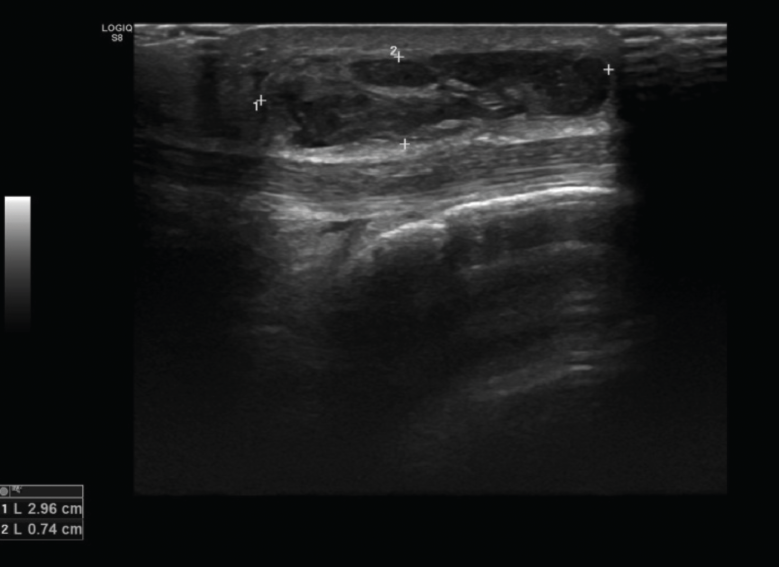

2.2. Roturas

Se observan áreas hipoecoicas de solución de continuidad de las fibras tendinosas(7), con retracción de los márgenes con la contracción muscular cuando la rotura tendinosa es completa (Figuras 9 y 10).

Figura 9. Corte sagital de una ecografía de rodilla: foco hipoecoico por rotura parcial del tendón cuadricipital.

Figura 10. Corte sagital de una ecografía de rodilla: ausencia del tendón rotuliano por rotura completa, con hematoma señalado en el trayecto del tendón.